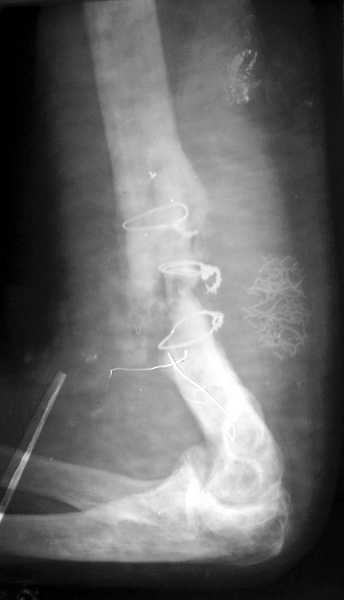

Второй случай, также после множественных операций:

пластина, аппарат, серкляж и парез нерва.

Также ревизия, из-за низкого состояния доступ был

сделан через остеотомию локтевого отростка.

Ложный сустав фиксирован двумя локинг плейт с

аутокостной пластикой, также через два месяца увидели признаки консолидации.

Движение в суставе разрешили в две недели.